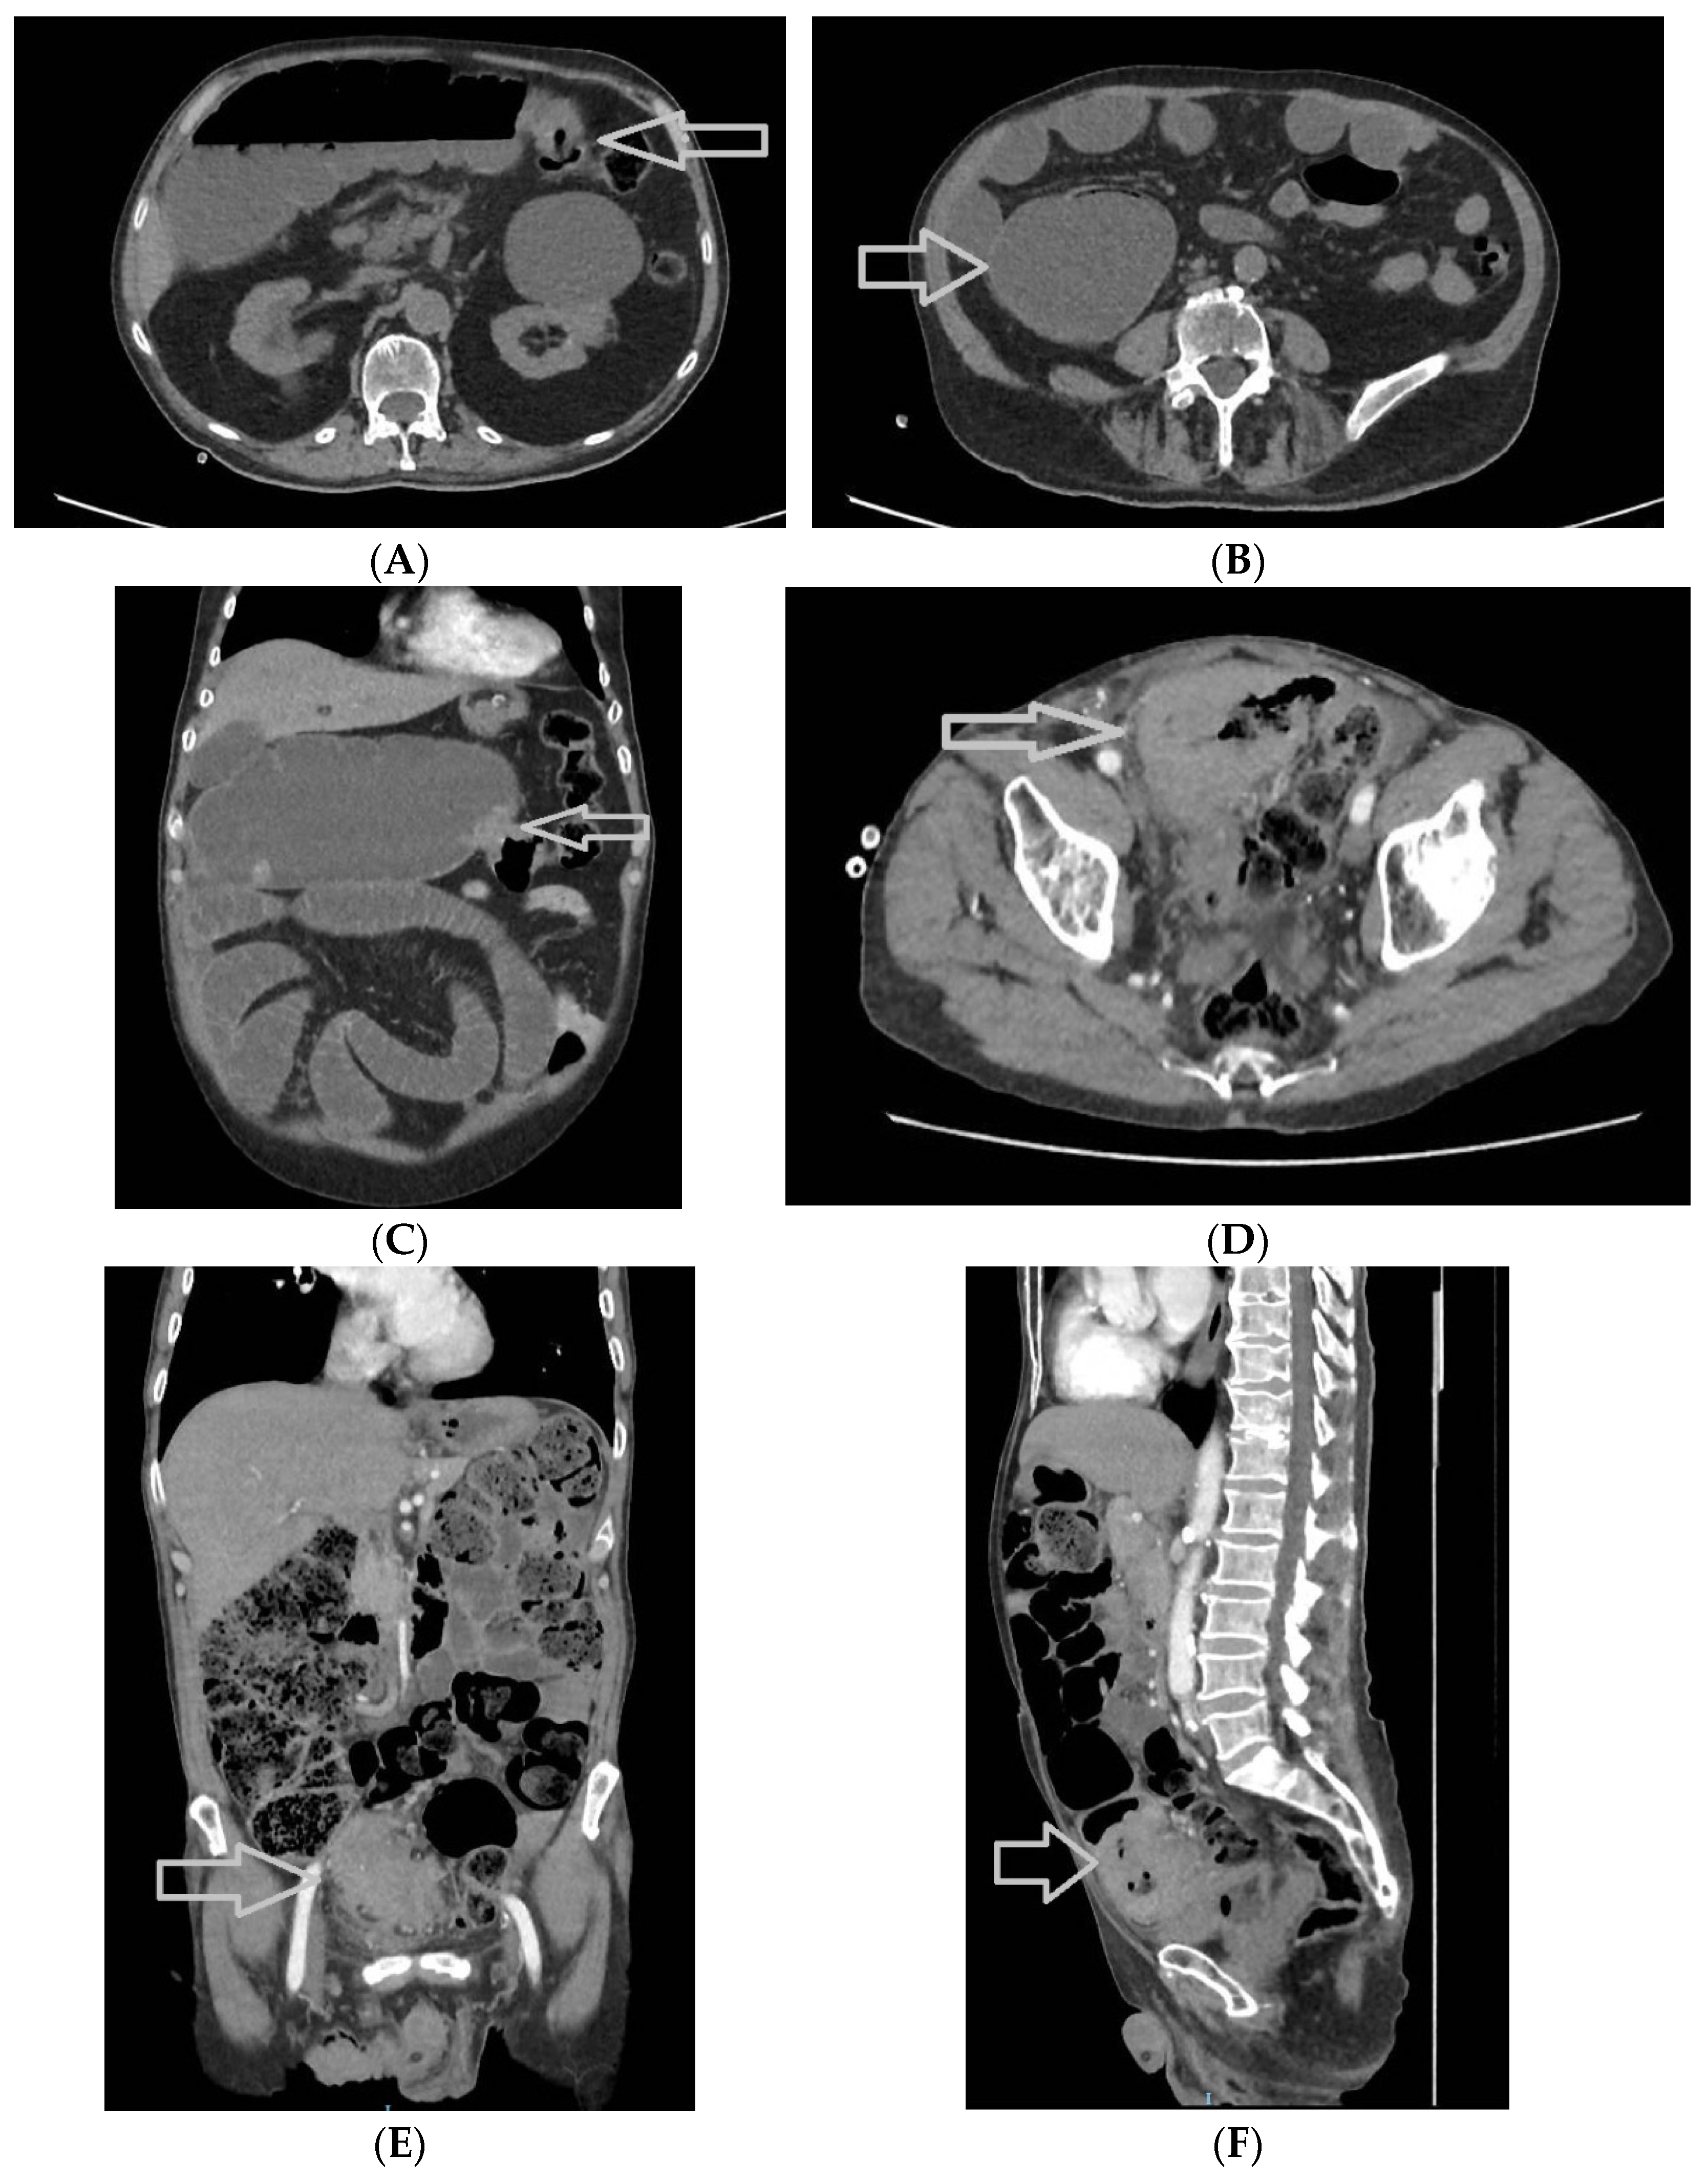

- left colon (including the splenic flexure, descending colon, and sigmoid colon), consisting of 47 patients, 30.7% of the study group (Figure 9);

- -

- rectum (including the rectosigmoidian junction (Figure 10), superior rectum, medium rectum, inferior rectum and anus), consisting of 67 patients, 43.8% of the study group.